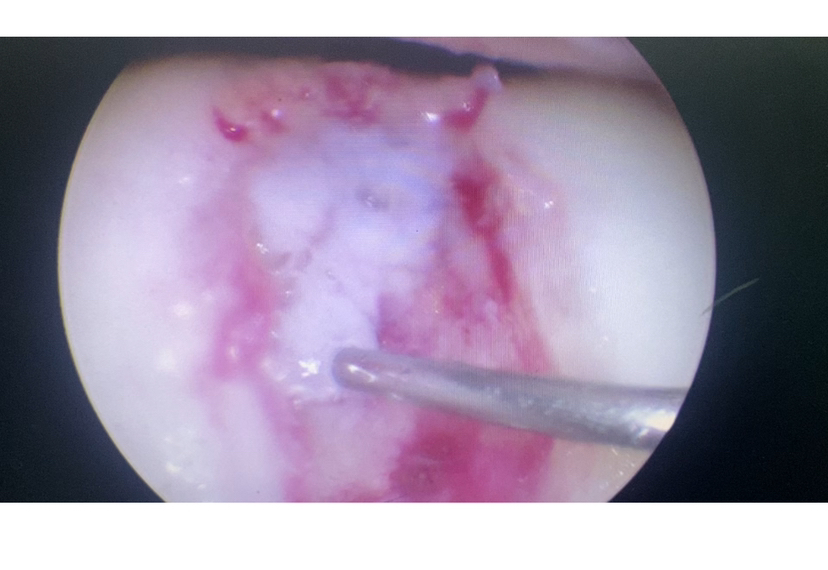

清理微骨折处理

滑车软骨损伤 (软骨剥脱,软骨下骨暴露)